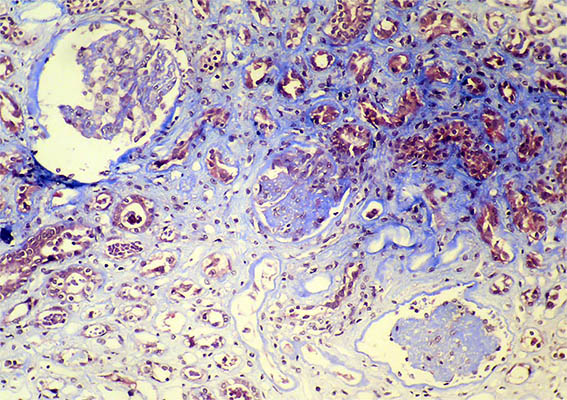

Se hace biopsia renal con impresión diagnóstica de lesión renal aguda. Ver las imágenes.

Figura 1. Trcrómico de Masson, X100.

Figura 2. Tricrómico de Masson, X200.